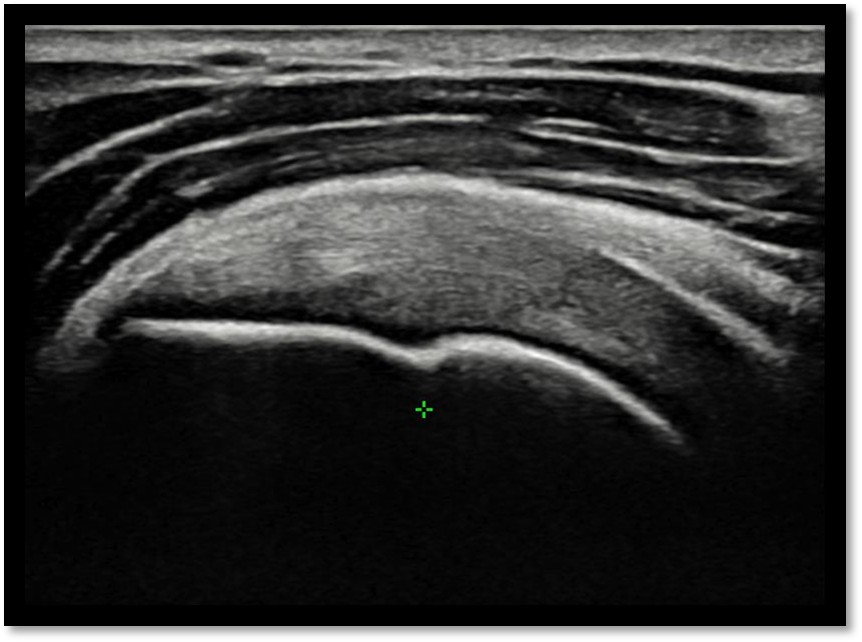

MRI와 초음파를 다시 검토했습니다.

회전근개 극상건의 관절면측(articular-side) 부분파열.